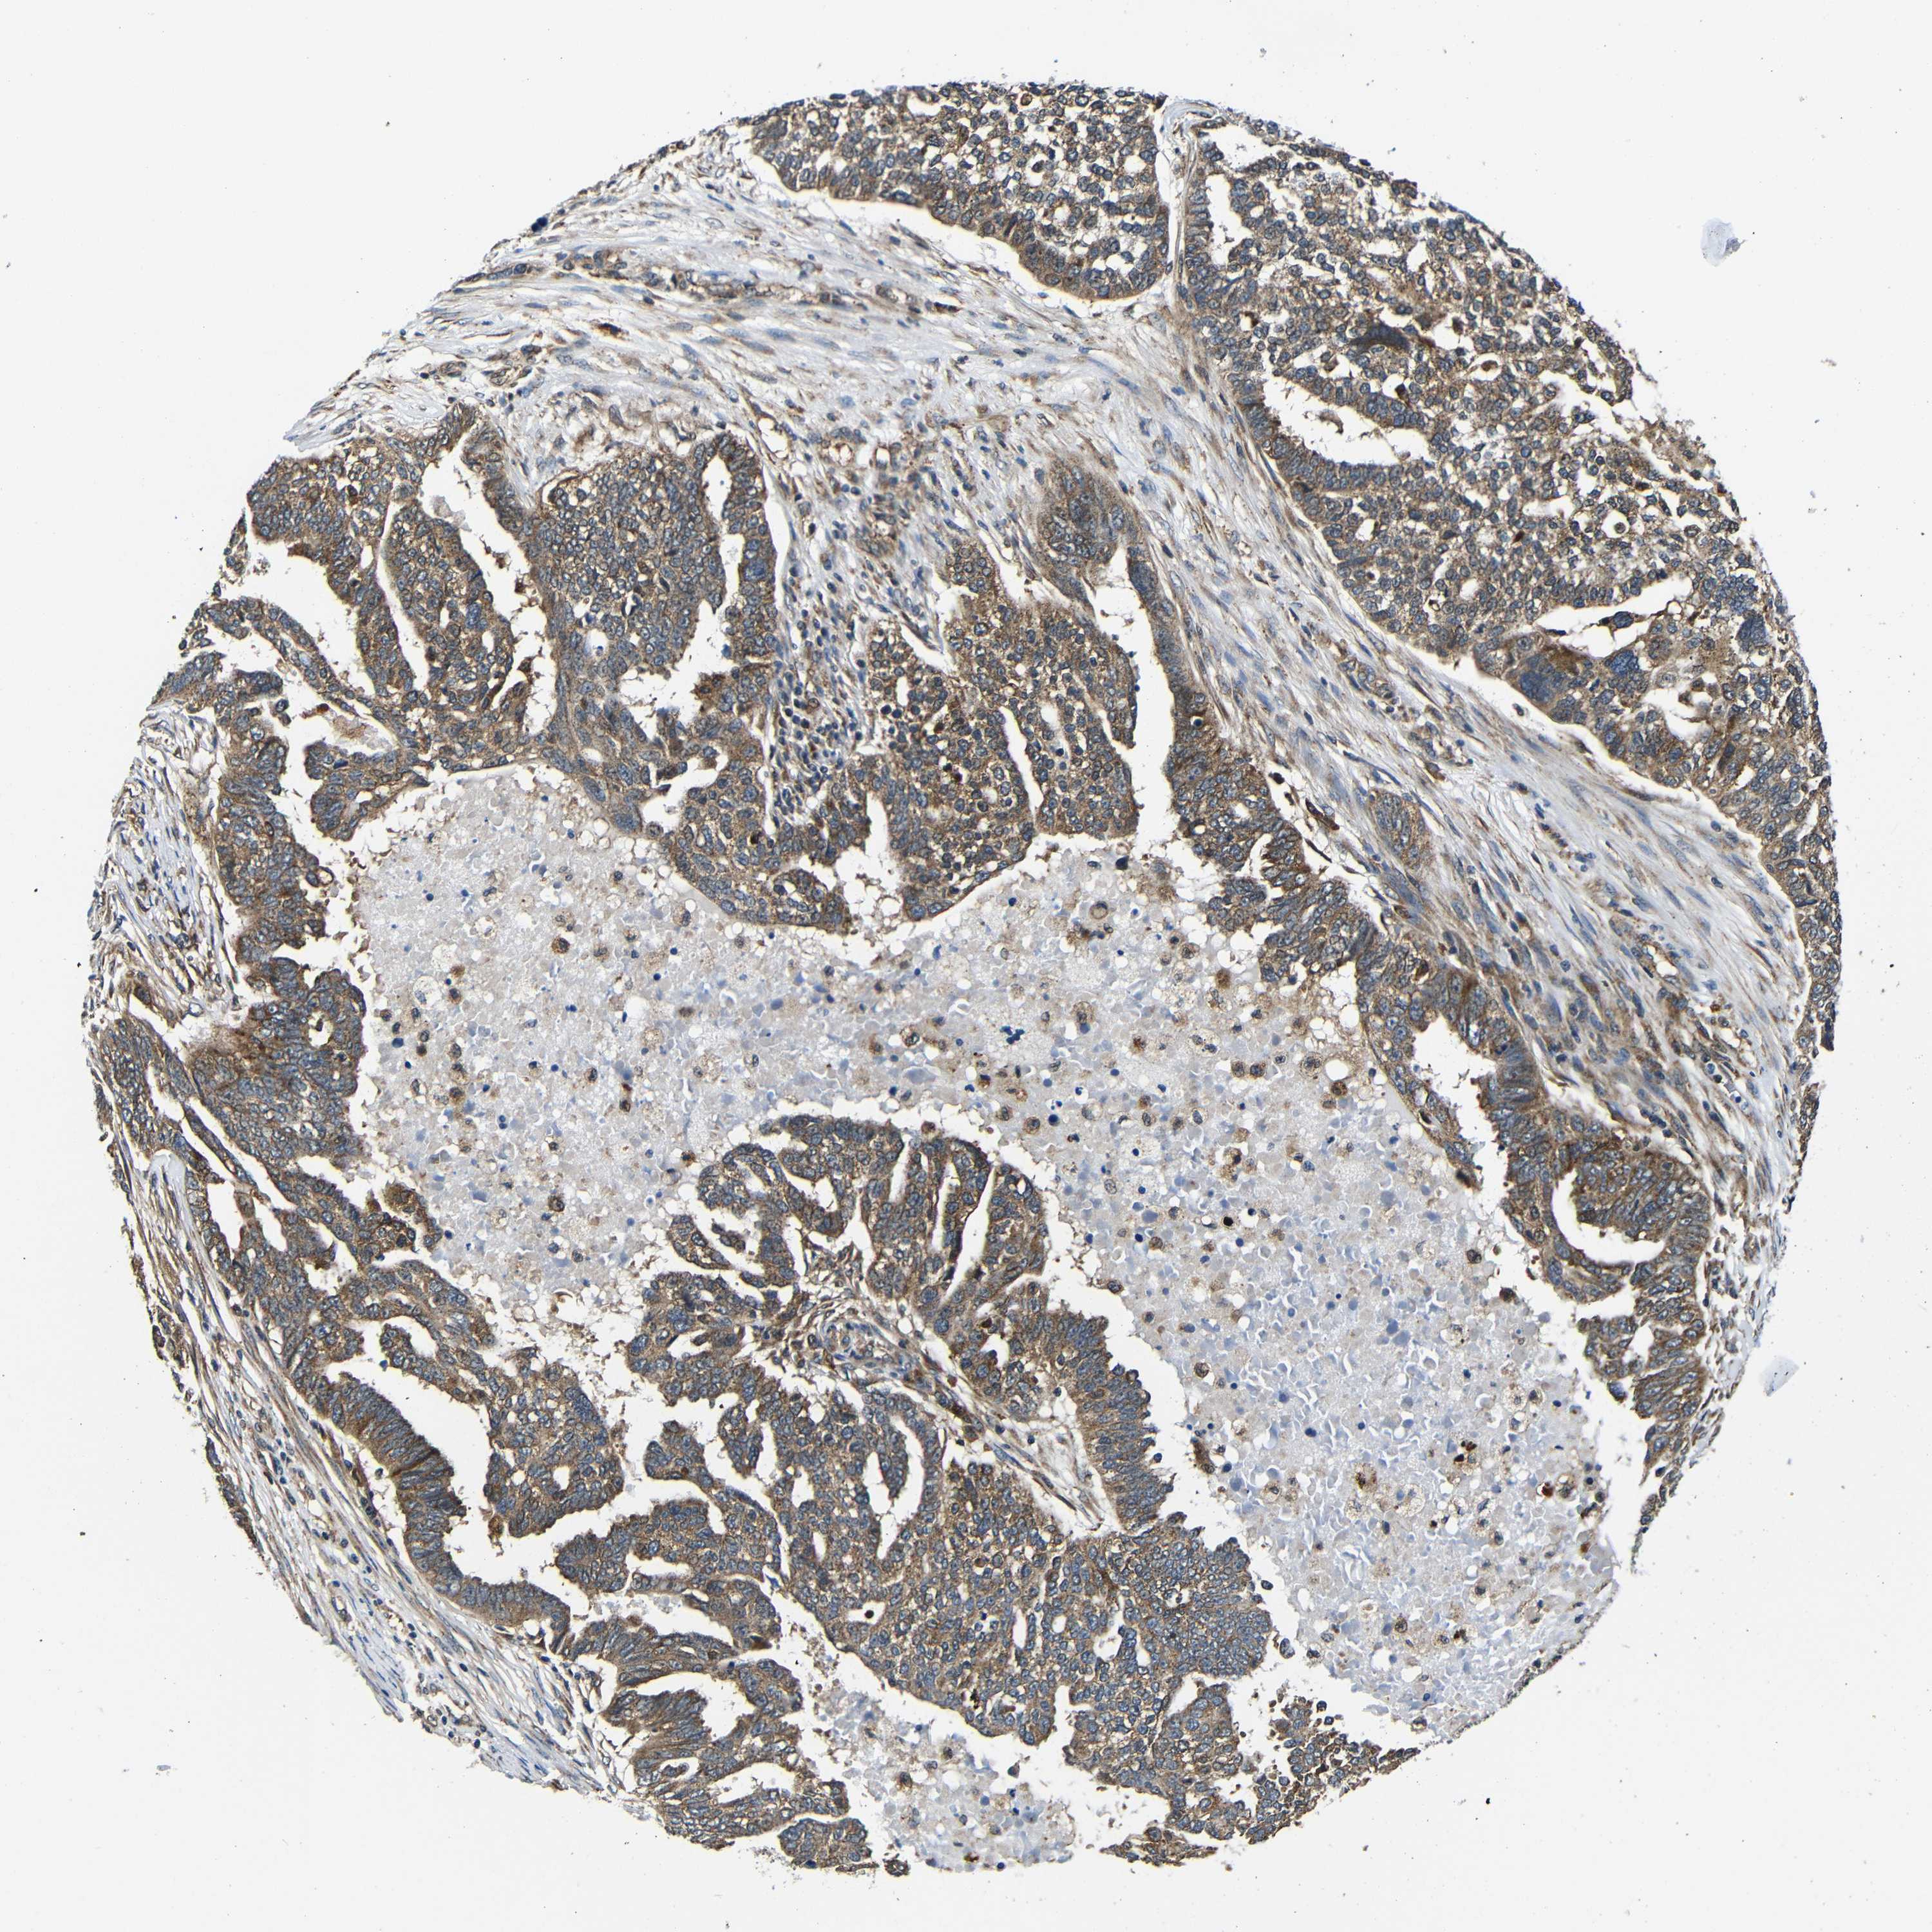

OVARIAN CANCER - Protein expressioni

A mouse-over function shows sample information and annotation data. Click on an image to view it in a full screen mode. Samples can be filtered based on level of antibody staining by selecting one or several of the following categories: high, medium, low and not detected. The assay and annotation is described here.

Note that samples used for immunohistochemistry by the Human Protein Atlas do not correspond to samples in the TCGA dataset.

Antibody stainingi

Antibody staining in the annotated cell types in the current human tissue is reported as not detected, low, medium, or high, based on conventional immunohistochemistry profiling in selected tissues. This score is based on the combination of the staining intensity and fraction of stained cells.

Each image is clickable and will lead to virtual microscopy that enables deeper exploration of all samples and also displays staining intensity scores, fraction scores and subcellular localization as well as patient and tissue information for each sample.

Antibody CAB012476

Staining

High

Medium

Low

Not detected

Intensity

Strong

Moderate

Weak

Negative

Quantity

>75%

75%-25%

<25%

None

Location

Nuclear

Cytoplasmic/membranous

Cytoplasmic/membranous,nuclear

Cystadenocarcinoma, serous, NOS

Carcinoma, endometroid

Cystadenocarcinoma, mucinous, NOS

Carcinoma, NOS